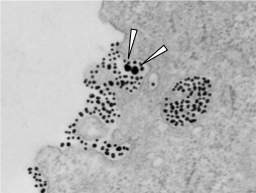

| Credit: Hongbo Pang. |

In a study published in Nature Communications, University of Minnesota researchers discovered a novel cellular process that can engulf nanomaterial without direct peptide functionalization, and its activity is regulated by Cysteine surrounding the cells. The research team termed this cellular process of engulfing bystander NPs as ‘bystander uptake.’

“By simply mixing two types of nano-sized material, we discover a novel cellular process that offers an easy solution for nanomaterial entry into cells,” said Hongbo Pang, corresponding author, an assistant professor in the College of Pharmacy and a member of the Masonic Cancer Center. “Moreover, it opens up a new avenue of cell biology that interconnects several fundamental elements of living cells. Further understanding of this process will aid in both cell biology and nanotechnology development.”

the bystander uptake only allows the cells to engulf nano-sized materials, but not other substances surrounding the cells (e.g. fluids);

the activity of this bystander uptake is stimulated by the existence of one of 20 natural amino acids, Cysteine, surrounding the cells.

These phenomena have been validated with a wide variety of cells, nanoparticles (aka nanomaterials), and under various physiological conditions.

co-administration with TAT-NP, a peptide and nanomaterial fusion, enables cells to engulf nano-sized materials in a bystander manner;

this bystander uptake is specific to nanomaterial, but not other substances surrounding the cells;

cysteine in the cell culture medium greatly stimulates the activity of this bystander uptake.